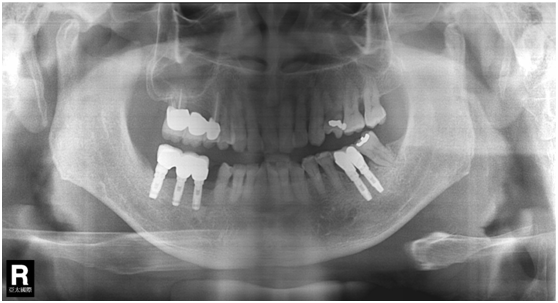

患者之後於96/11/08在右下第一小臼齒與植體間有膿胞產生,並於97/02/21確認右下第一小臼齒有根裂的情形,因此在97/02/29拔除此牙;經過將近半年後,於97/09/23放置一顆植體於此位置

97/02/21 確定根裂時拍的片子

97/02/21

97/09/18 拔牙半年後安排右下第一小臼齒植牙前

97/09/23 右下第一小臼齒植牙完成時

98/01/08經過三個半月做右下第一小臼齒的二階暴露,發覺鄰牙的植體高度竟已掉下來